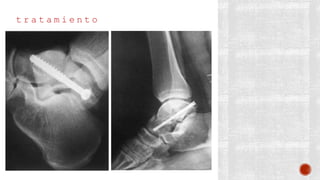

t r a t a m i e n t o

¬ Osteocondrales

- Quirúrgico por artroscopia

Reposición del cartílago

Se pueden utilizar tornillos de

Kirschner perpendiculares al trazo de

fractura

Se coloca un yeso corto de 8 a 12

semanas en el posoperatorio; en

apoyo sin carga